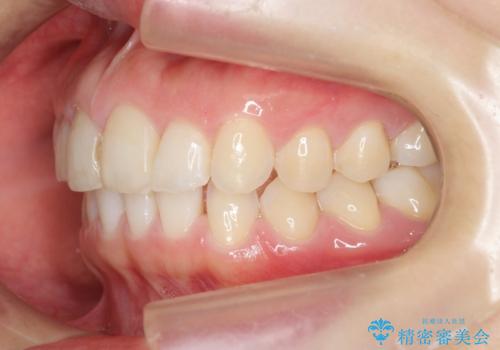

前歯のガタつきをきれいに マウスピース矯正治療

- 「前歯のガタつきをきれいにしたい。」と矯正治療を希望され来院されました。

前歯のガタつきをワイヤー部分矯正、上顎前突の咬合関係を後方移動することで理想的な咬合関係を確立します。

上顎の全体的な後方移動を実現するためにマイクロインプラントを併用したゴムかけを行ったことで理想的な咬合関係を確立することができました。